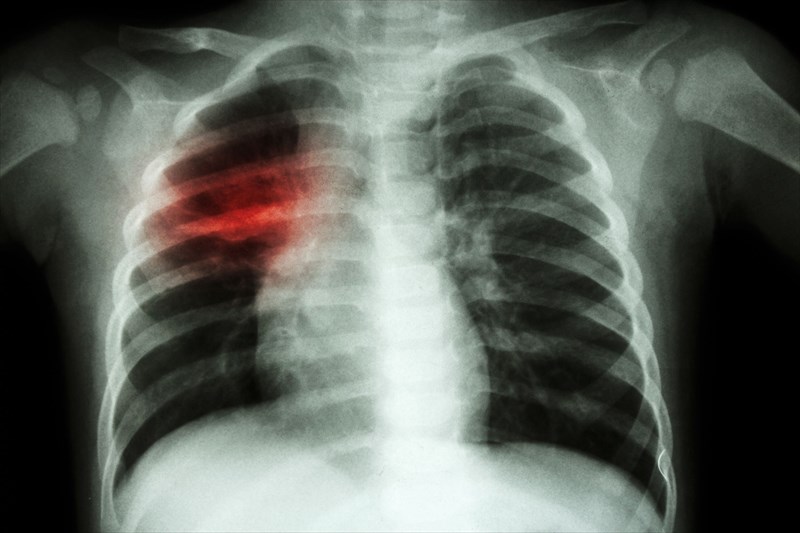

Illustration showing human lungs affected by tuberculosis (TB)